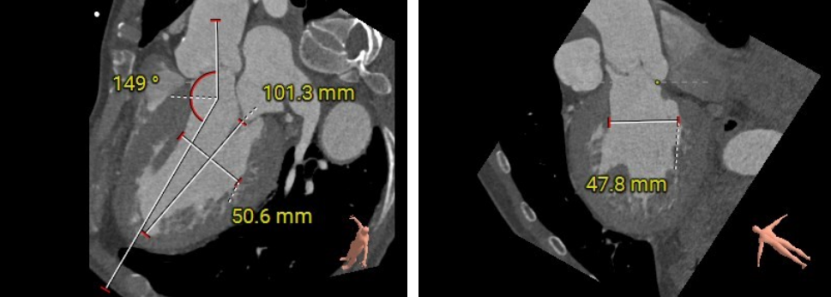

术前CT评估

Type I型三叶瓣,大瓣环,主动脉窦部扩张,近似横位心,双侧冠脉点状钙化。

(入路概览)

输送器可调弯30°左右。

TypeI型三叶瓣,近似横位心,大瓣环,采取全麻下,超声全程引导无放射线TAVR,超声下完成临起置入,导丝经心尖入路跨瓣入降主动脉,扩张鞘预扩,输送器顺导丝至主动脉窦上方,瓣膜定位及释放,术后功能评估等操作。